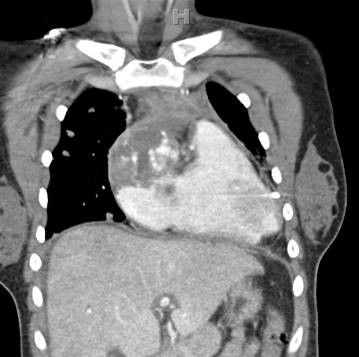

CT Chest: A mass is centered in the epicardium of the right atrial wall. It involves the pericardium and has extended through the myocardium to fill the right atrium. A small pericardial effusion exists. There is a small right pleural effusion, a heterogeneous appearance of the liver, and a small volume ascites. Numerous small masses are seen in the lung fields.